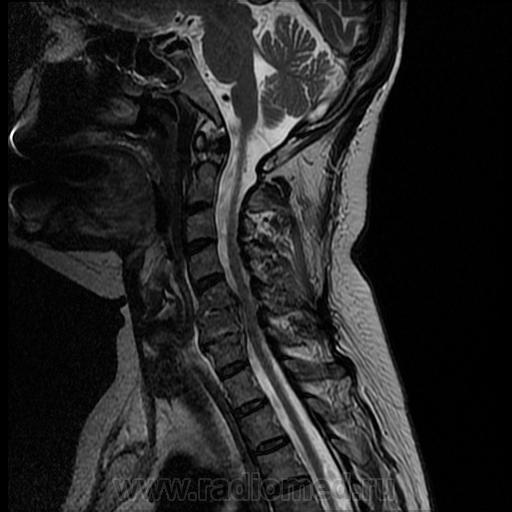

- КТ или МРТ;

Возбудители туберкулезного спондилита (микобактерии туберкулеза) проникают в позвоночные структуры гематогенным или лимфогенным путем из первичного воспалительного очага.

Местом жизнедеятельности патогенных микроорганизмов чаще становится губчатое вещество тел позвонков. Значительно реже поражаются их дуги и отростки. Предрасполагающими факторами к развитию туберкулезного спондилита являются травмы, например, вывихи или компрессионные переломы позвонков.